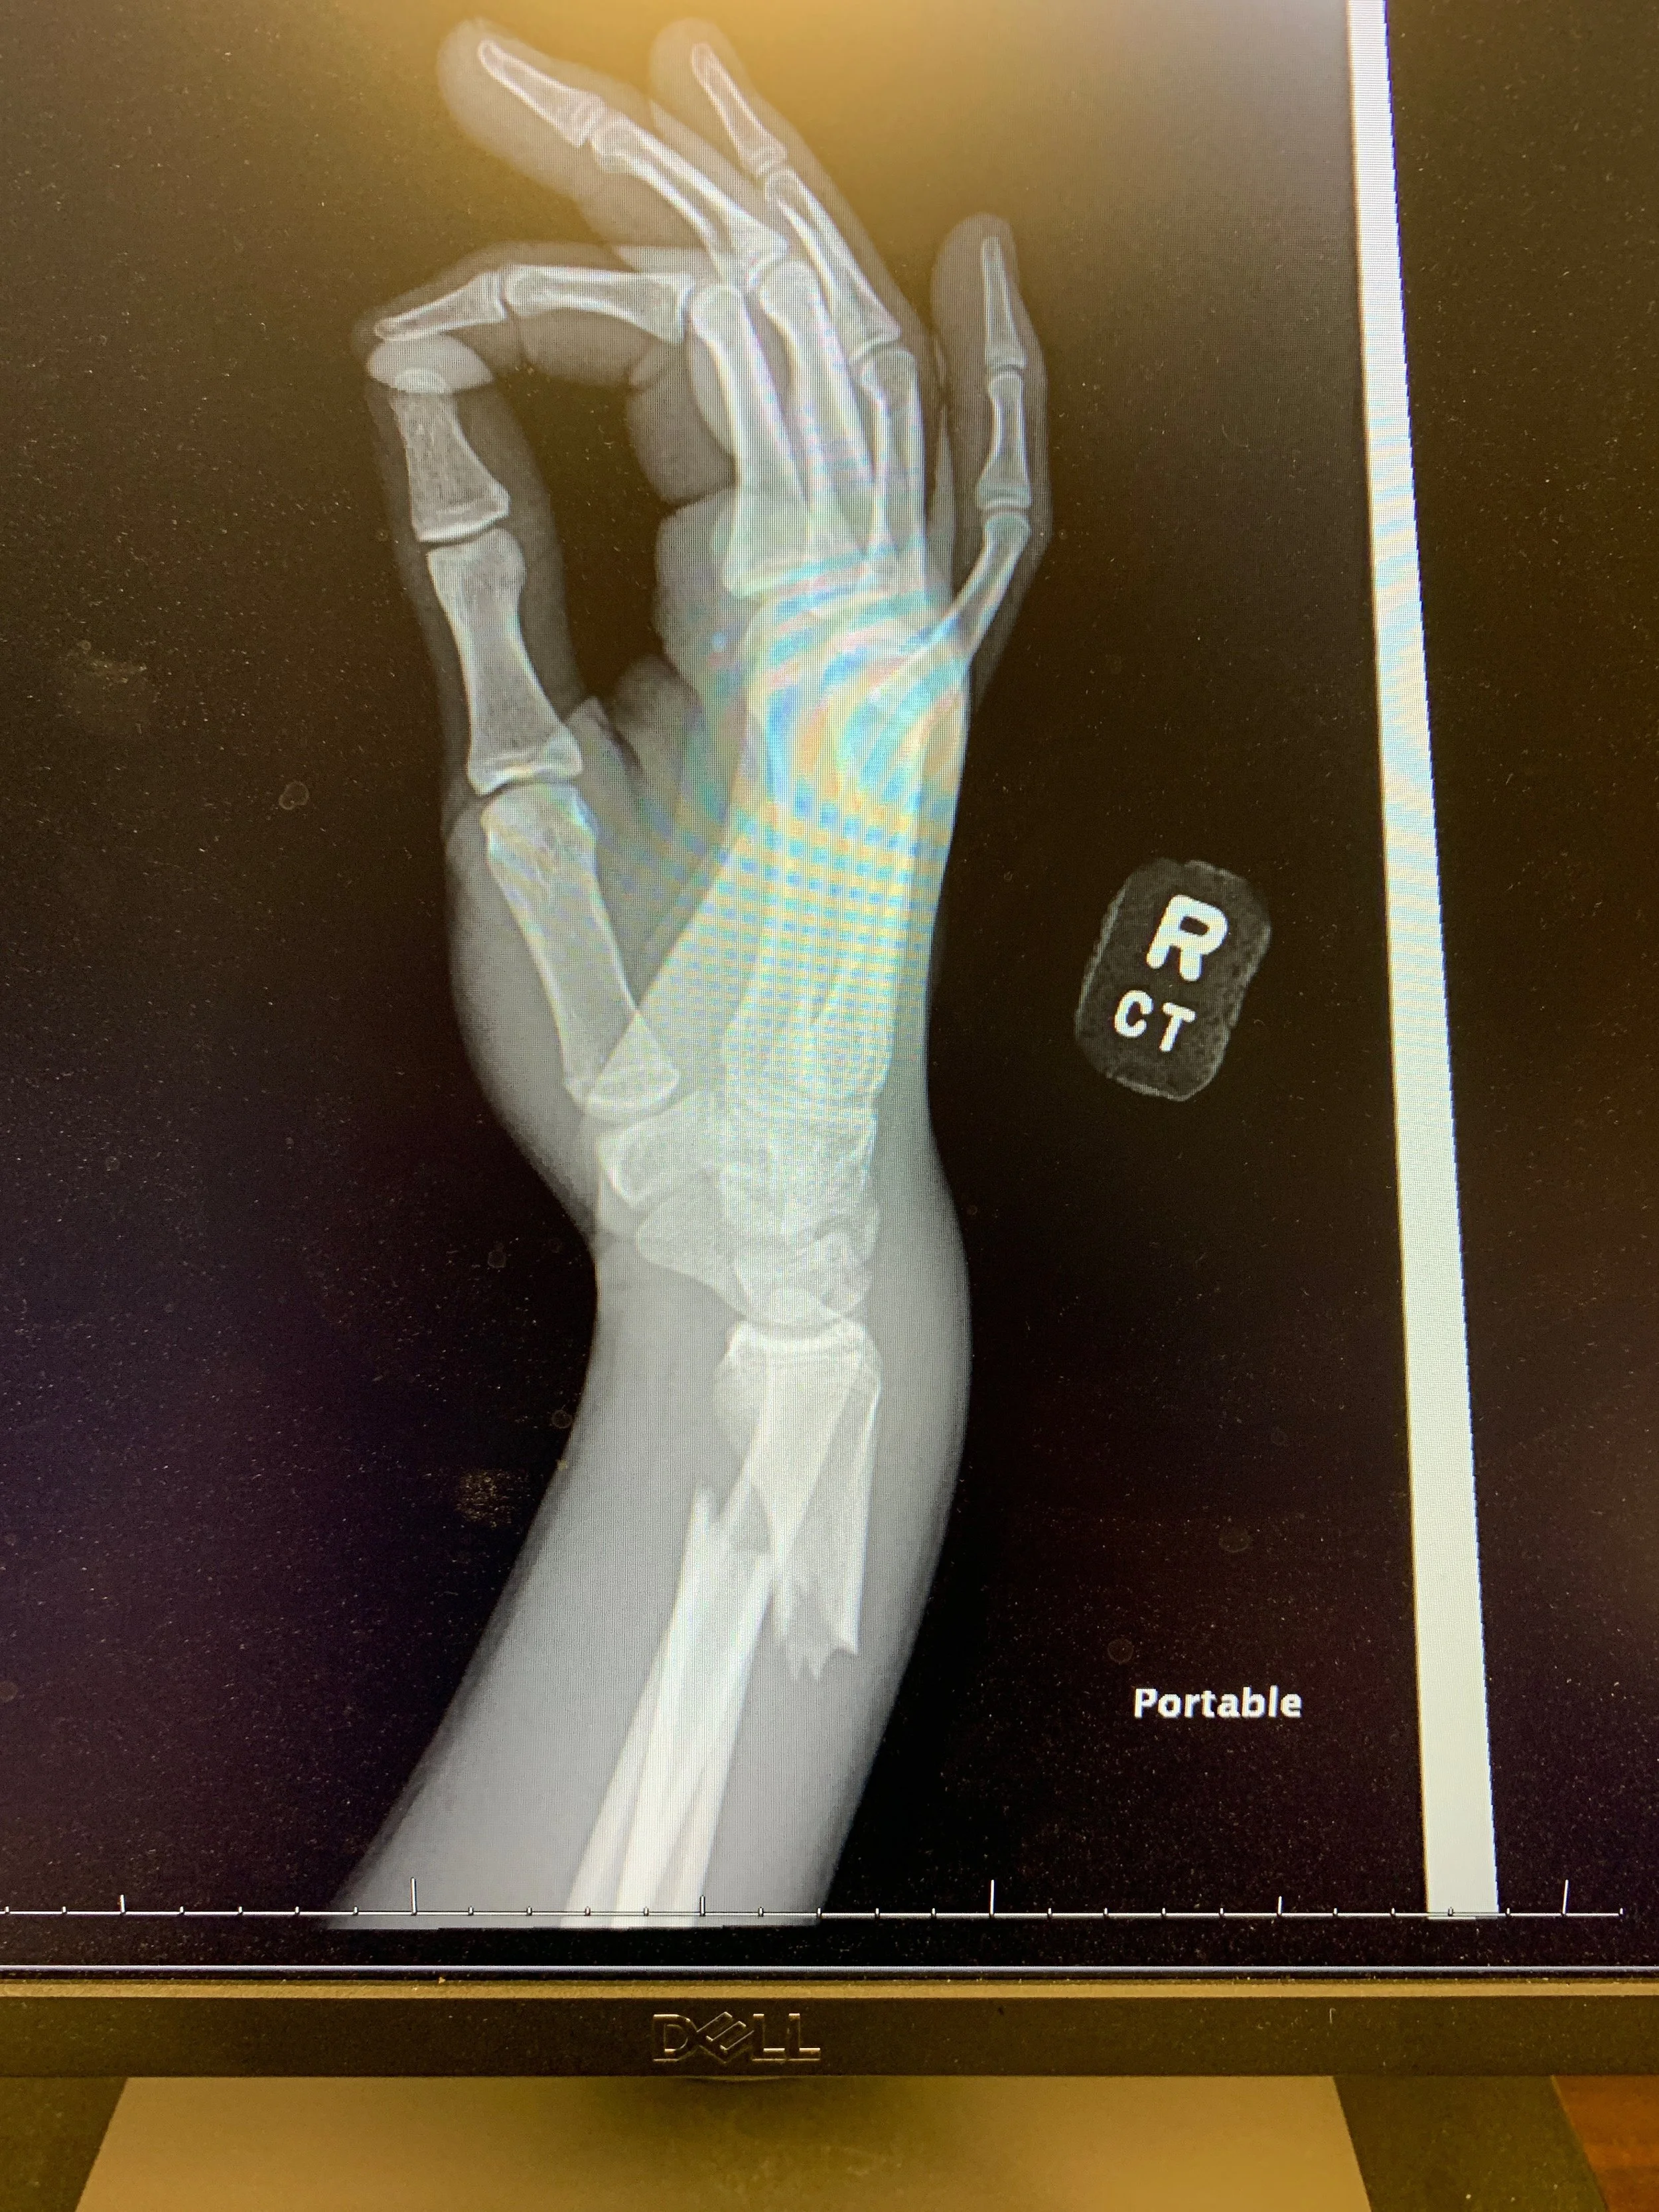

Several weeks ago my son was at the High Point Racetrack at Mount Morris, Pa. He was practicing for the state championship series, and was very happy with the pace he was setting as the day was starting. Already wrapping up the 250cc championship at our local Latrobe Raceway Supercross track, he set his sights on the motocross track the pros ride. All the hopes of a great series came crashing to an end when he did, coming up short on a triple jump. He didn’t even realize the damage that was done and picked the bike right up to continue. Then he noticed his arm wouldn’t “work” anymore. Sometimes pain doesn’t hit right away. Almost breaking through the skin, his radius was broken and his wrist ligaments injured. Looking at him, I could clearly see how badly this break was. There was nothing straight about it.

We went to Mercy Hospital in Pittsburgh and were admitted into the ER. They made short work of X-rays and diagnosing the problem. The trouble was that it was broken so badly and in an odd place that they couldn’t correctly set the bone. I sent the X-ray photo to friends and family who were praying for my boy. They too were shocked. He was in total agony as they continued to try to get the two pieces of bone in place. Two full grown men pulled in opposite directions with everything they had, but were not strong enough to pull his wrist end far enough away from the elbow end to get the break line to properly meet. The fracture was unable to be correctly set. It was too much to me to watch, and his pain was almost enough to make him pass out. Surgery would be required, something he really didn’t have the time for as a teenager bent on getting the rest of the state championship season completed.